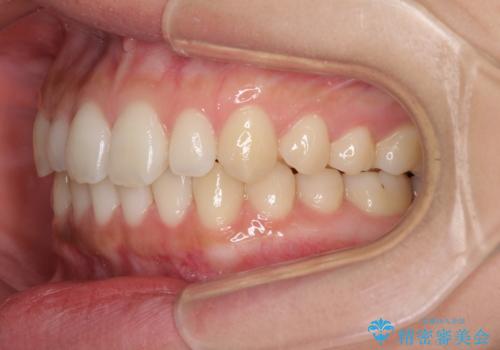

海外勤務中でも矯正治療 インビザラインによる軽度叢生改善

- 前歯のデコボコを気にして来院された患者様です。

治療期間中に海外勤務になる可能性が高いことが分かっていましたが、矯正治療を始めたいとのことでしたので、インビザラインを用いて治療することとしました。

通常であれば半年から10ヶ月程度で終了する歯並びでしたが、海外に長期出張することになったため、1年10ヶ月の期間を要しました。

出張に行かれてしまうと追加のマウスピースを発注できないため、マウスピースの交換頻度を低くし、一時帰国のタイミングに合わせていくことで、スムーズに進めて行くことができました。